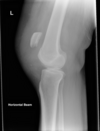

2

1. Tunnel views: used to detected tibial spine fractures and loose bodies within the notch 2. Oblique views: helpful for tibial plateau fractures 3. Sunrise views: essential in evaluating for patellar fractures 4. A/P: evaluate for subluxation, fracture, dislocation, joint space narrowing, foreign bodies